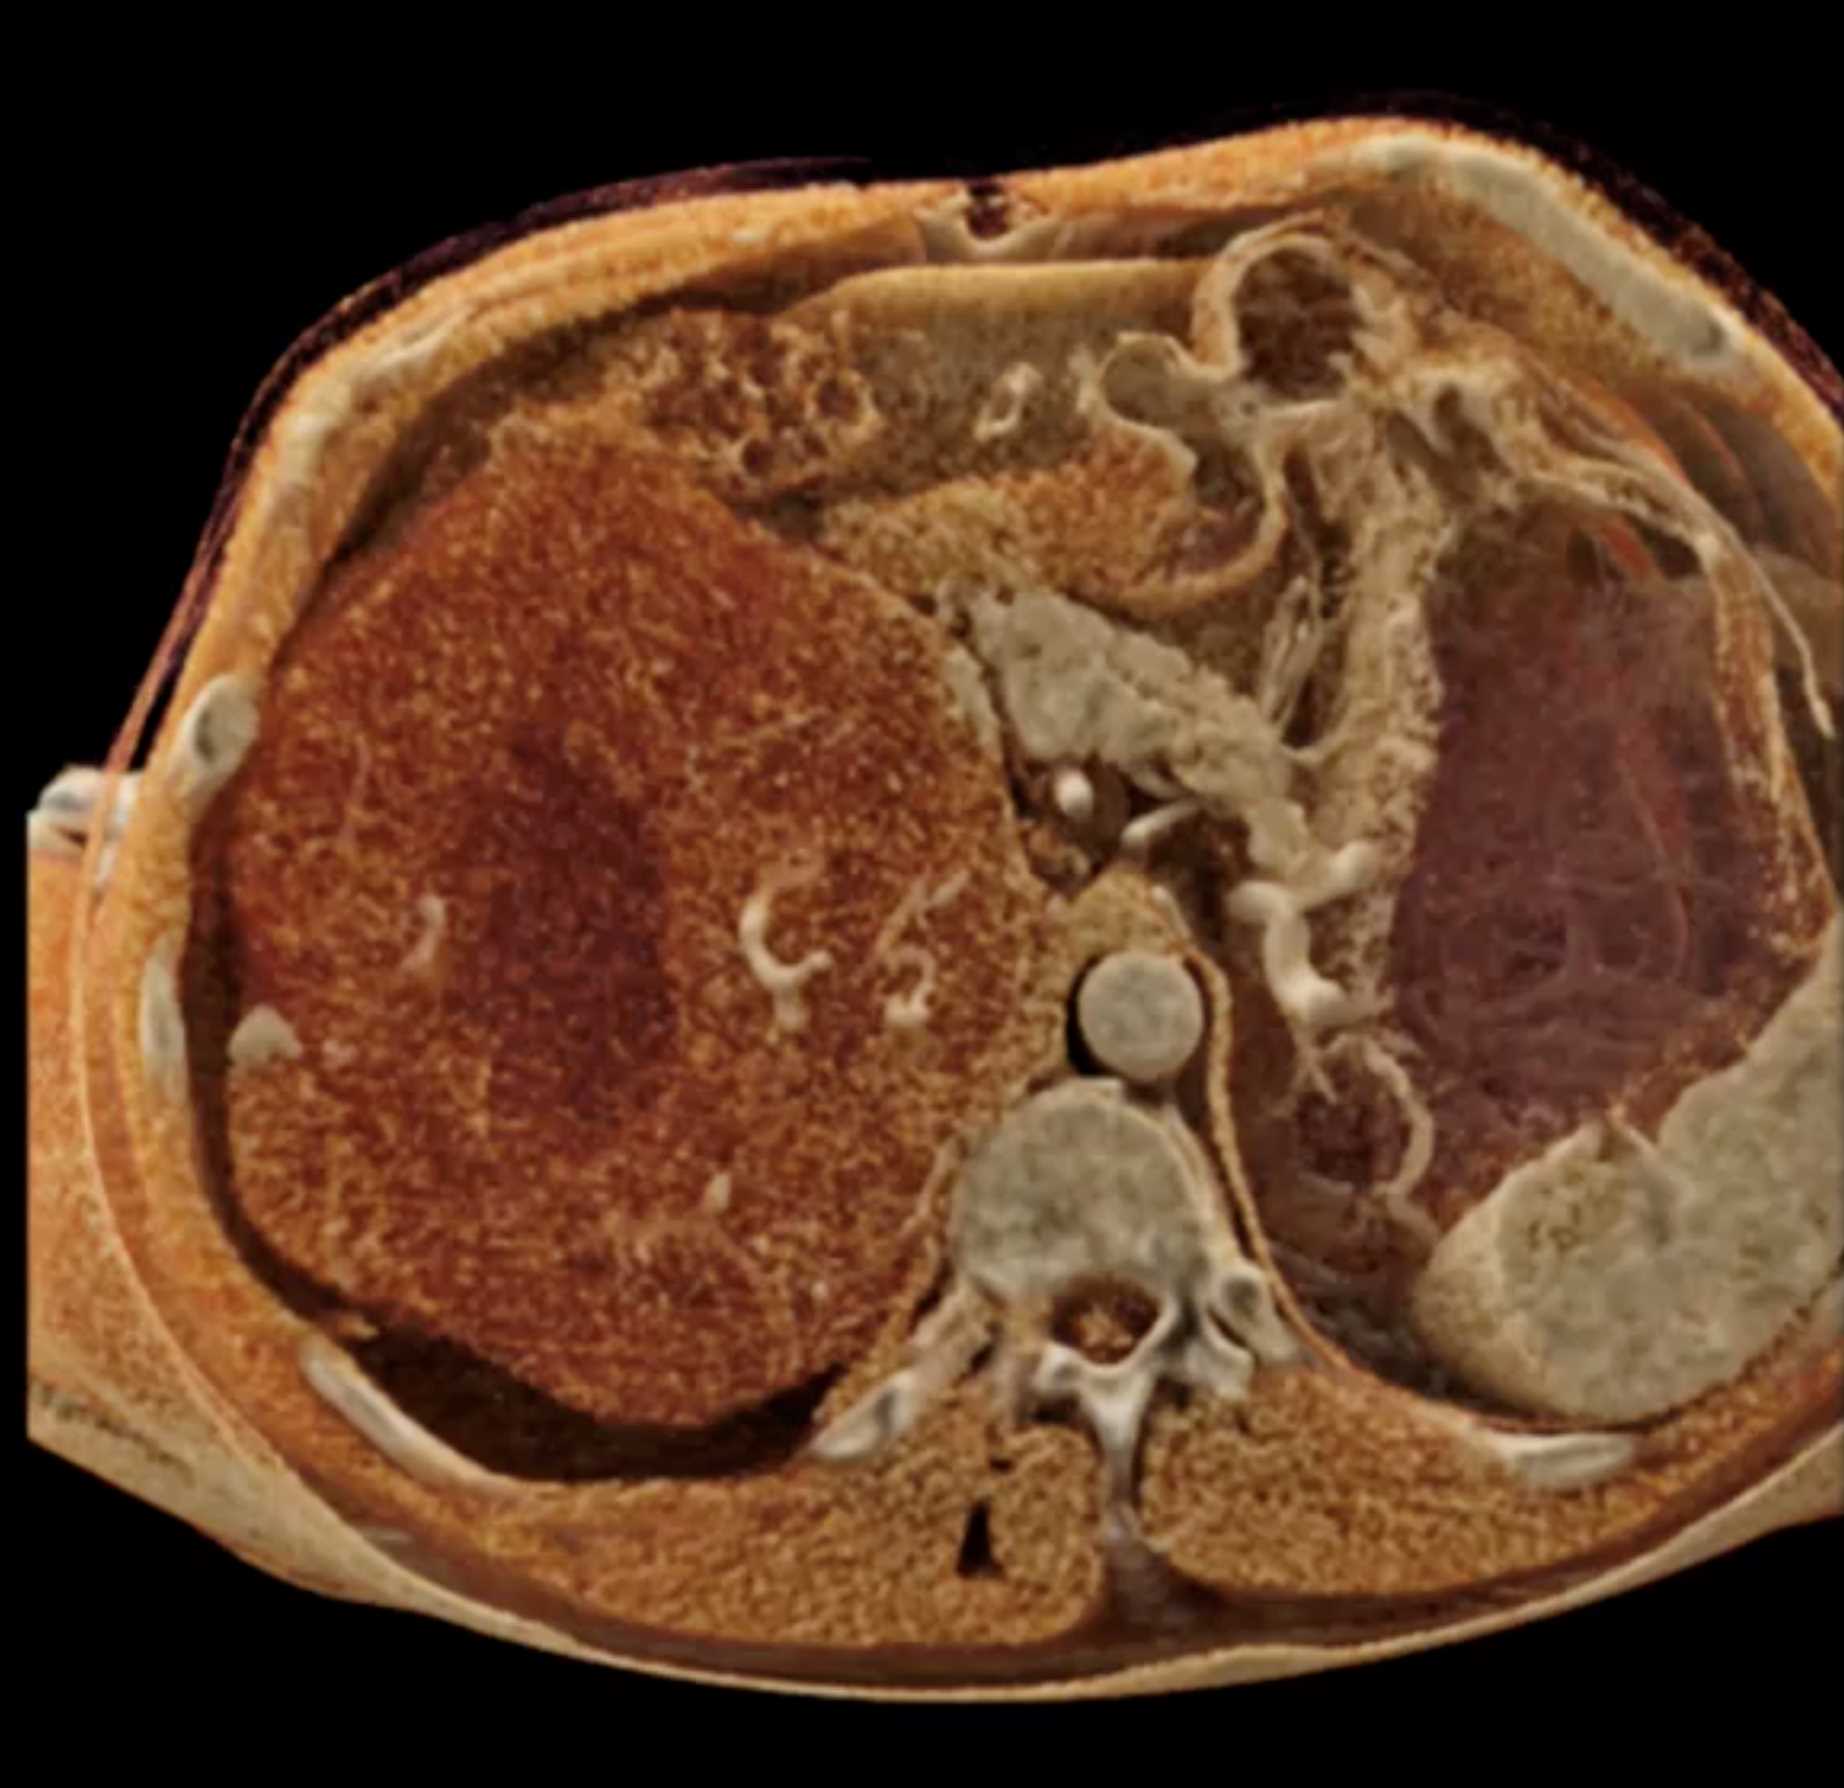

Left Adrenal Metastases from Renal Cell Carcinoma